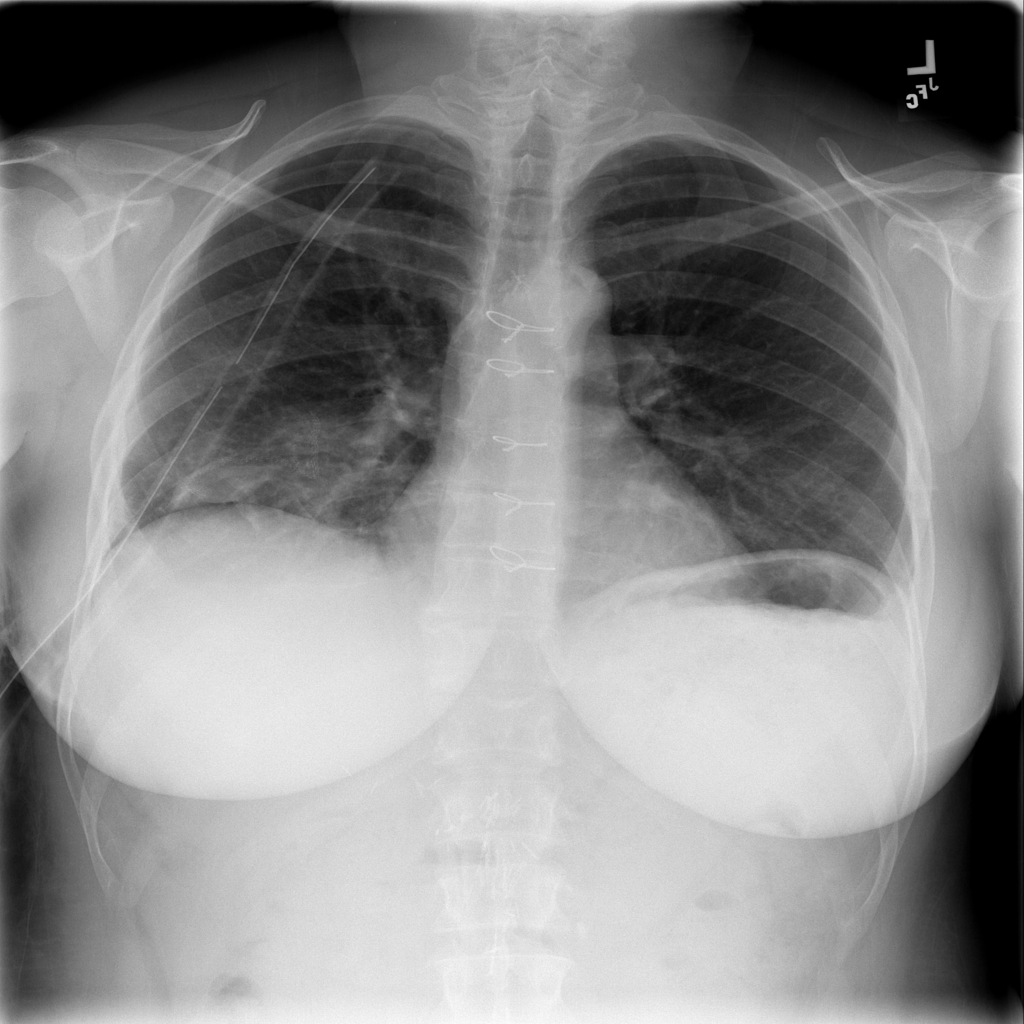

Pneumothorax

Pneumothorax means air is present outside the lung in the pleural space, which can allow part of the lung to collapse. It is an important imaging finding because the size and clinical impact can vary widely.

Showing up to 90 reference images for Pneumothorax.